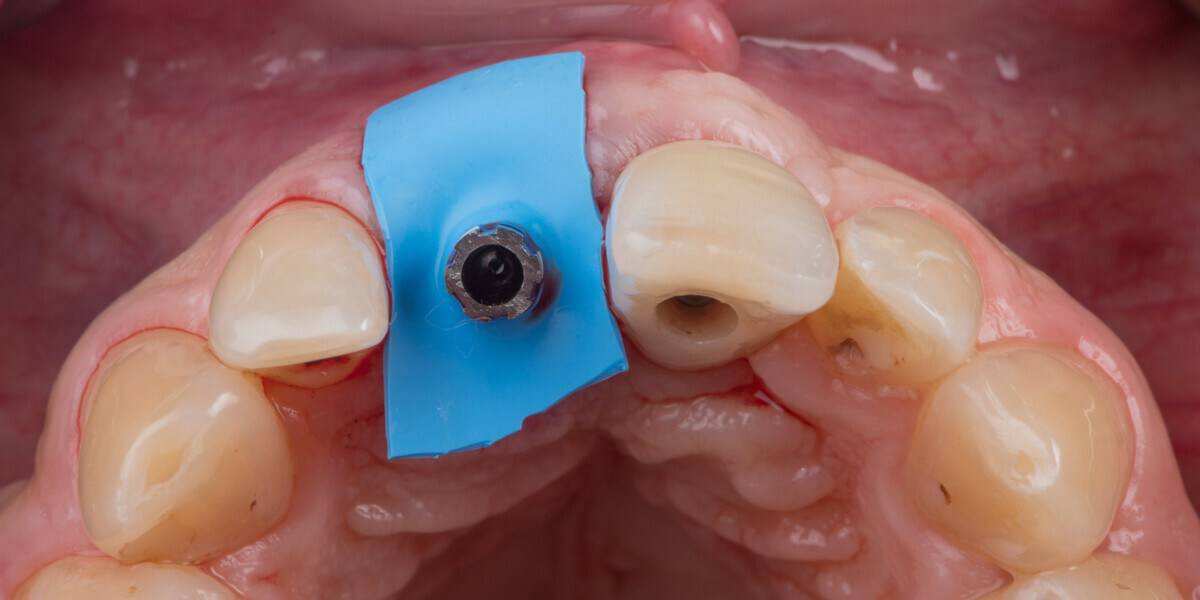

Immediate placement and restoration of a Straumann BLX implant replacing maxillary incisors